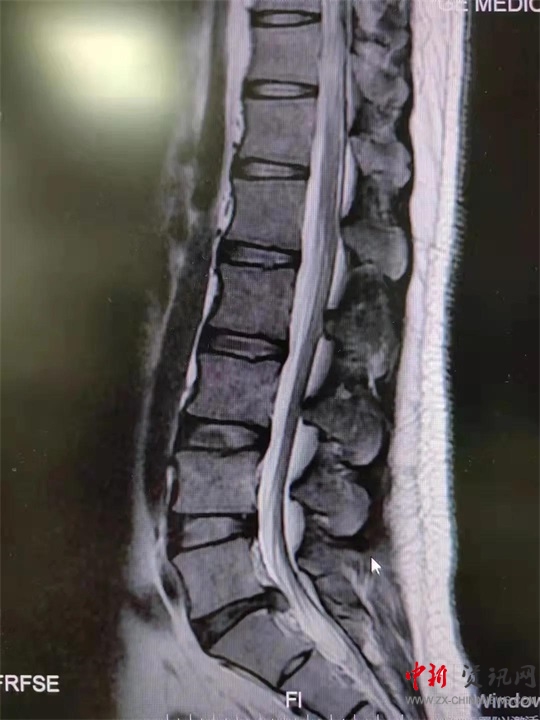

9月初,盧先生來到駐馬店市第一人民醫(yī)院就診。影像學檢查提示腰5骶1椎間盤突出。患者癥狀、體征與影像學表現(xiàn)相符,腰椎間盤突出癥診斷明確。結合患者情況,蔣學國主任團隊決定舍棄傳統(tǒng)手術方案,為患者實施UBE技術下腰椎間盤髓核摘除術,這也是UBE技術在西院區(qū)的首次應用。